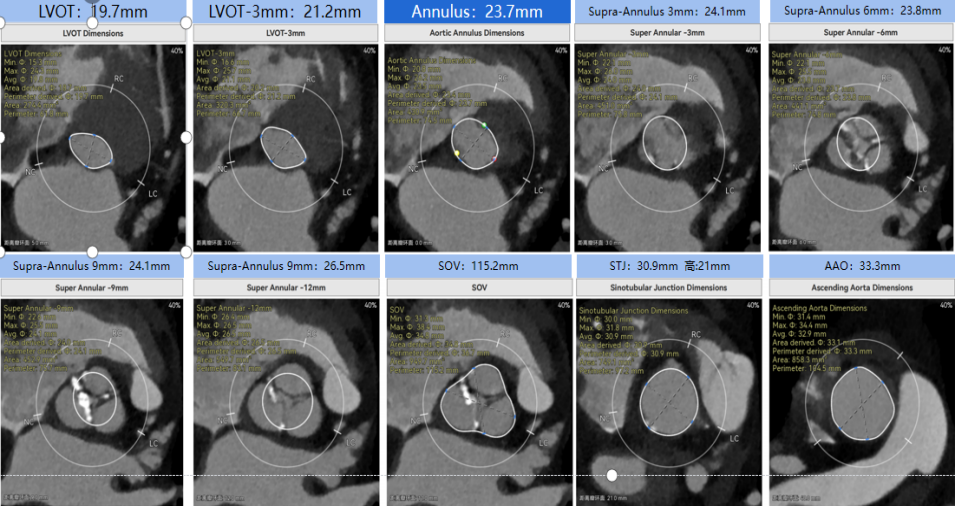

患者病史 男性,74y, 因 “发现心脏瓣膜病 1 年,加重伴喘气半年” 入院。门诊检查显示主动脉瓣重度AS并伴轻-中度AR。患者基础疾病较多:胸腹主动脉多发穿透性溃疡、心功能III级等,手术指征明确,但风险极高。 术前CT LVOT- Annulus 倒梯形,对植入瓣膜有挤压位移风险,Annulus直径23.7mm,瓣叶增厚,钙化集中在无冠窦边缘。 左冠脉开口高度可,瓣叶不长、窦部空间较大,无冠脉风险;室间隔膜部较短,有一定PPI风险,心脏角度37.9°;心室较小,有一定循环崩溃风险,术前注意补液。 术前造影角度及入路:血管入路散在钙化、无迂曲;主动脉弓条件好、双侧股动脉直径大、右股穿刺点侧壁存在环形钙化 左右重合位:RAO 7° CAU 21° 右窦中心位:LAO2 1° CAU 1° 手术策略 20mm球囊预扩后植入AV26瓣膜,同时做好预防循环崩溃、传导阻滞的应急预案。 术中挑战 1)球囊预扩:20mm球囊预扩时无明显 “腰征”,但存在少量反流,提示瓣膜钙化与解剖结构对扩张的阻力不均 2)首次释放偏差:第一次定位释放时,瓣膜在 “开花” 过程中下滑约 3mm,工作位观察显示小弯侧瓣周漏较多(深度超过完全覆膜区),需二次调整。 3)二次精准定位:以猪尾导管为参照,将定位点调整至 “猪尾 - 2mm” 处,结合真实窦底深度(较深)重新释放,最终瓣膜位置稳定,瓣周漏显著减少。 术后即刻效果: 瓣膜形态良好,跨瓣压差从术前的 67mmHg 降至 6mmHg,且无明显瓣周漏,冠脉开口通畅; Commisural Alignment 术后即刻超声: Prostyle A®预装干瓣——助力临床最优化解决方案: √ 平衡的径向支撑力:特殊的解剖结构下位置形态良好,术后跨瓣压差大幅降低,血流动力学改善明显; √ 80%可回收设计:支持术中二次调整释放位置,保证精准释放; √ 平衡的收腰设计&Commissural Alignment设计: 为患者后期冠脉PCI保留了生命通道;